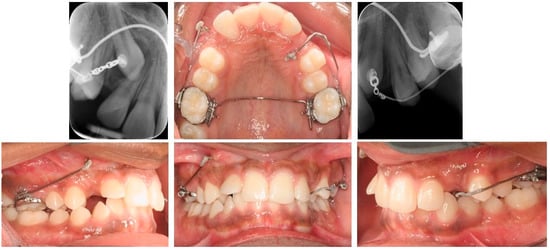

3.1. Buccal Impaction

3.2. Palatal Impaction